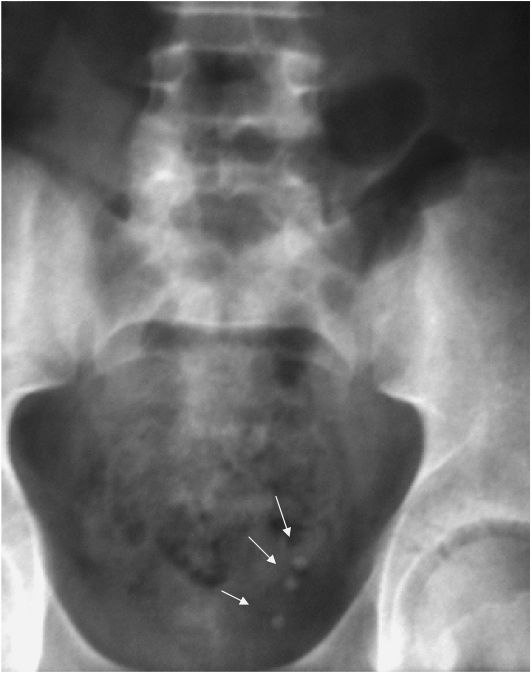

Изображения КТ конкрементов мочевого пузыря